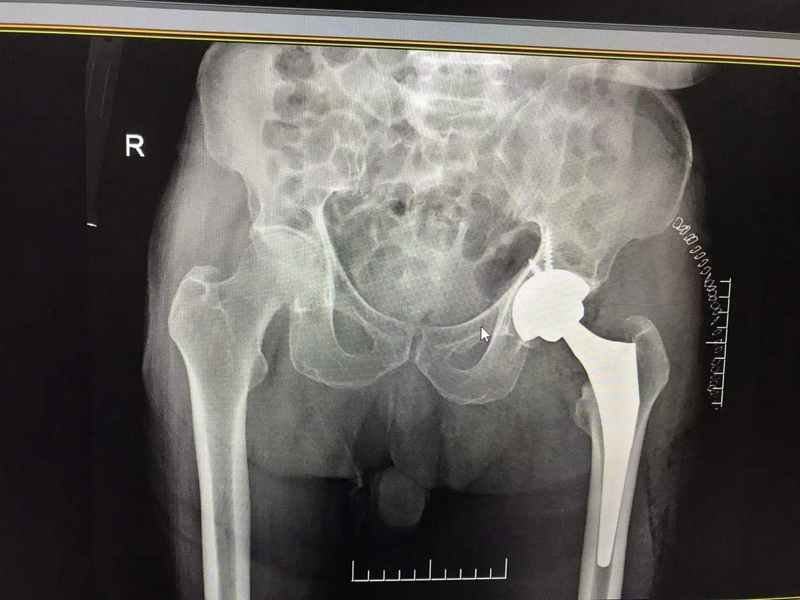

術(shù)后髖關(guān)節(jié)假體位置佳